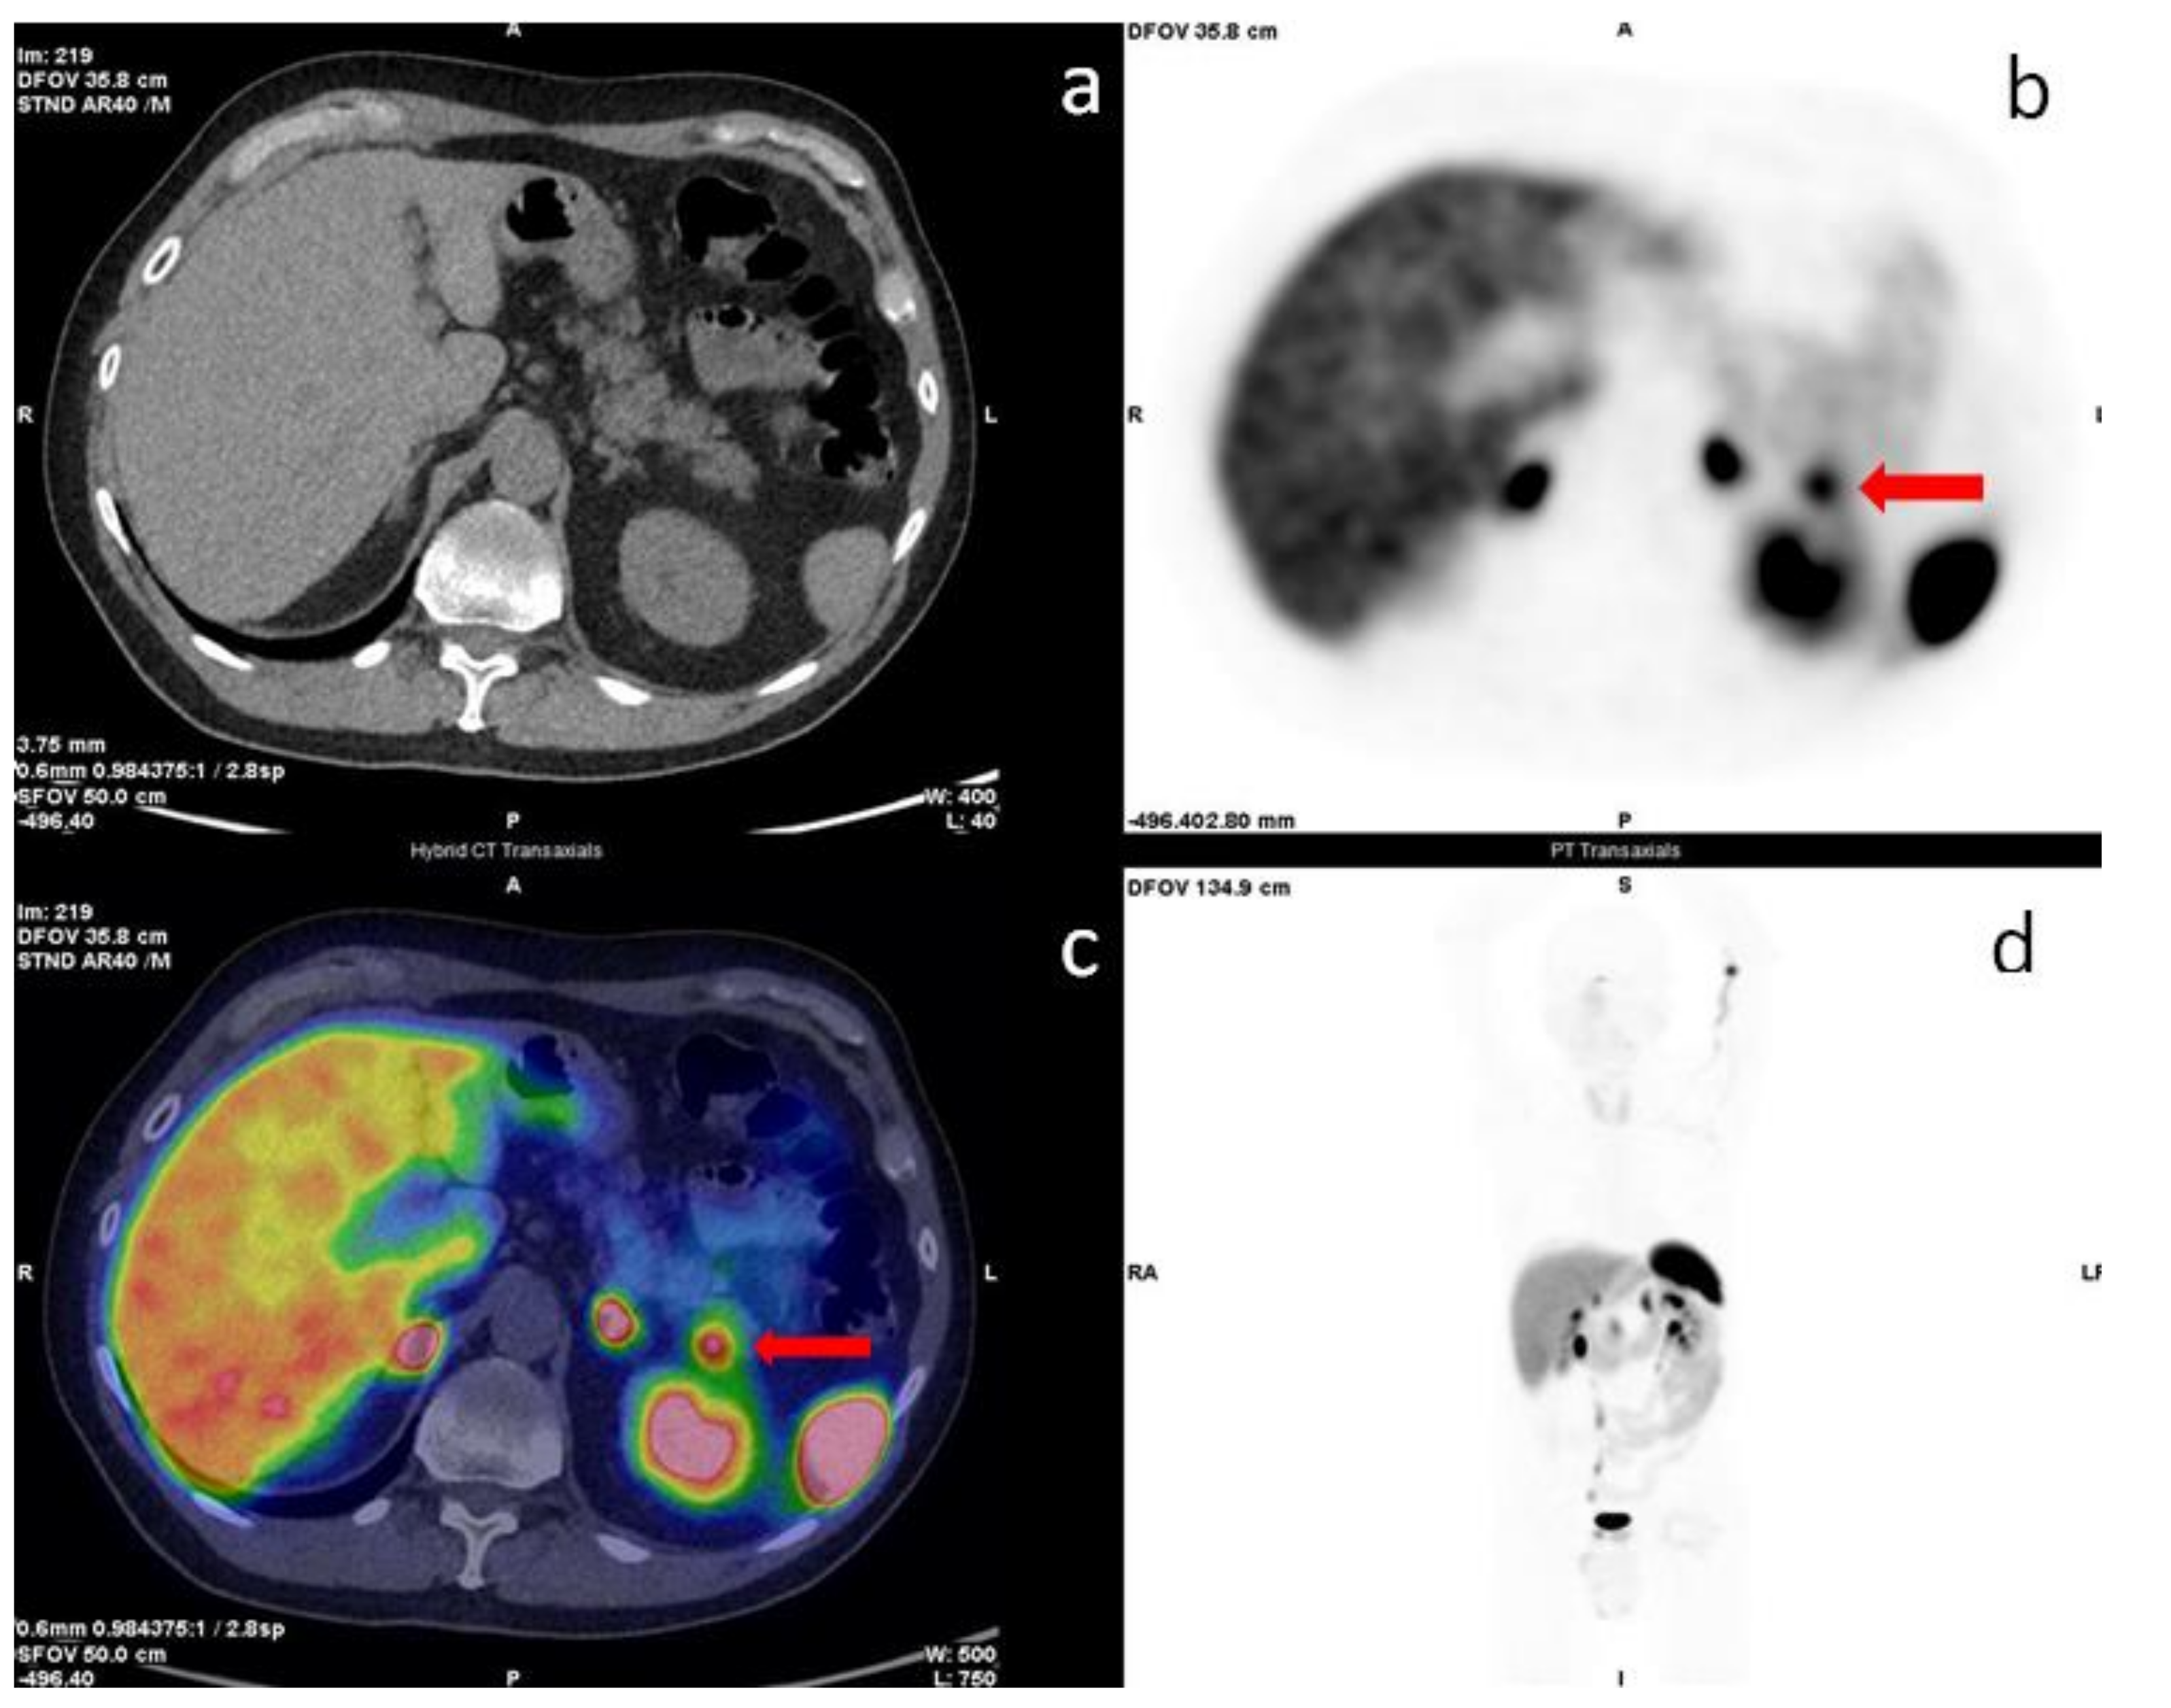

- Cingarlini, S.; Ortolani, S.; Salgarello, M.; Butturini, G.; Malpaga, A.; Malfatti, V.; D’Onofrio, M.; Davì, M.V.; Vallerio, P.; Ruzzenente, A.; et al. Role of combined 68Ga-DOTA-TOC and 18F-FDG positron emission tomography/computed tomography in the diagnostic workup of pancreas neuroendocrine tumors. Pancreas 2017, 46, 42–47. [Google Scholar] [CrossRef]

- Paiella, S.; Landoni, L.; Tebaldi, S.; Zuffanter, M.; Salgarello, M.; Cingarlini, S.; D’onofrio, M.; Parisi, A.; Deiro, G.; Manfrin, E.; et al. Dual tracer (68Ga-DOTATOC and 18F-FDG) PET/CT scan and G1–G2 nonfunctioning pancreatic neuroendocrine tumors: A single center retrospective evaluation of 124 nonmetastatic resected cases. Neuroendocrinology 2022, 112, 143–152. [Google Scholar] [CrossRef]

- You, H.; Kandathil, A.; Beg, M.; De Blanche, L.; Kazmi, S.; Subramaniam, R.M. Ga-68-DOTATATE PET/CT and F-18 FDG PET/CT in the evaluation of lowand intermediate versus high-grade neuroendocrine tumors. Nucl. Med. Commun. 2020, 41, 1060–1065. [Google Scholar] [CrossRef]

- Evangelista, L.; Ravelli, I.; Bignotto, A.; Cecchin, D.; Zucchetta, P. Ga-68 DOTA-peptides and F-18 FDG PET/CT in patients with neuroendocrine tumor: A review. Clin. Imaging 2020, 67, 113–116. [Google Scholar] [CrossRef]

- Carideo, L.; Prosperi, D.; Panzuto, F.; Magi, L.; Pratesi, M.S.; Rinzivillo, M.; Annibale, B.; Signore, A. Role of Combined [68Ga] DOTA-SST Analogues and [18F] FDG PET/CT in the Management of GEP-NENs: A Systematic Review. J. Clin. Med. 2019, 8, 1032. [Google Scholar] [CrossRef] [PubMed]

- Chan, D.L.; Pavlakis, N.; Schembri, G.P.; Bernard, E.J.; Hsiao, E.; Hayes, A.; Bailey, D.L.; Pavlakis, N.; Schembri, G.P. Dual somatostatin receptor/FDG PET/CT imaging in metastatic neuroendocrine tumours: Proposal for a novel grading scheme with prognostic significance. Theranostics 2017, 7, 1149. [Google Scholar] [CrossRef] [PubMed]